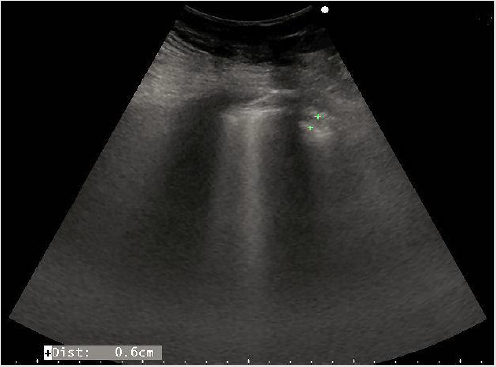

LU at admission assesed the presence of diffusively bilateral irregular and thickened pleural line with sliding reduction’s. Confluent B lines with white lung areas and some sub-pleural consolidations in the postero lateral areas (Figures 3 & 4), especially on the left side [10]. Pleural effusion on the left. The consolidations appeared as small ipo-iso echoic areas. We found a characteristic posterior distribution of the above features.

Figure 4: Shows a sub pleuric ipo-iso echoic consolidation, multiple B lines, pleural thickness and irregularities.